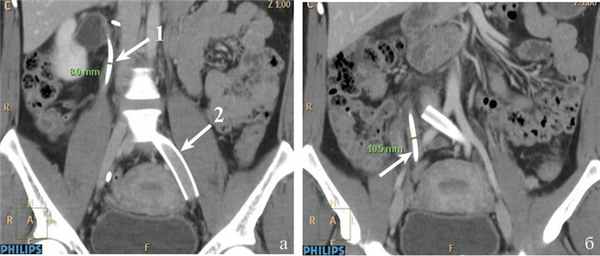

Для уточнения диагноза и определения тактики лечения выполнены ренофлебография, оварикография, тазовая флебография. По результатам флебографического исследования выявлены: сдавление правого мочеточника расширенной правой гонадной веной в верхней трети, расширение правого мочеточника в средней и нижней трети, стеноз левой наружной и общей подвздошной вен до 95% неопухолевого и нетромботического генеза, расширение левой внутренней подвздошной вены и ее притоков, депонирование контрастного вещества в варикозных венах малого таза (рис. 2). Рис. 2. Флебограммы пациентки М. а: 1 — правая гонадная вена; 2 — S-образный изгиб мочеточника в верхней трети; 3 — сдавление правого мочеточника правой гонадной веной; 4 — расширенный мочеточник в средней и нижней трети; б — стеноз общей подвздошной вены (указано стрелками). Случай расценен как синдром Мея—Тернера, тазовое венозное полнокровие, синдром правой гонадной вены. Учитывая выраженное сужение левых подвздошных вен, высокий риск развития венозных тромбоэмболических осложнений, первым этапом лечения решено выполнить эндоваскулярное стентирование левых подвздошных вен. Проведена имплантация стента Wallstent—Uni 14×60 мм. На контрольной флебографии определяется полная проходимость подвздошных вен (рис. 3). Рис. 3. Флебограмма пациентки М. Стент в левых общей и наружной подвздошных венах (указано стрелками). После стентирования проводили антикоагулянтную и дезагрегантную терапию (клексан 60 мг 2 раза в сутки под кожу живота, плавикс 75 мг/сут в течение 3 нед, затем клексан 40 мг/сут однократно). Постимплантационный период протекал без осложнений.

Учитывая выраженную диффузную кровоточивость тканей (пациентка получала низкомолекулярный гепарин в профилактической дозе), в забрюшинное пространство установлен силиконовый дренаж. Продолжительность операции составила 50 мин, кровопотеря — около 100 мл. Послеоперационный период без осложнений, дренаж удален на 1-е сутки после вмешательства. Через 2 дня после операции пациентка отметила значительное уменьшение болевого синдрома. При повторных ультразвуковых исследованиях и МСКТ на 3-й день послеоперационного периода сохранялись правосторонняя пиелоэктазия и расширение правого мочеточника, в связи с чем решено выполнить временное стентирование правого мочеточника (рис. 5). Рис. 5. Компьютерные томограммы пациентки М. после стентирования мочеточника. а: 1 — мочеточниковый стент в верхней трети; 2 — стент в правых подвздошных венах, проходимость его не нарушена; б — мочеточниковый стент в нижней трети (указано стрелками).